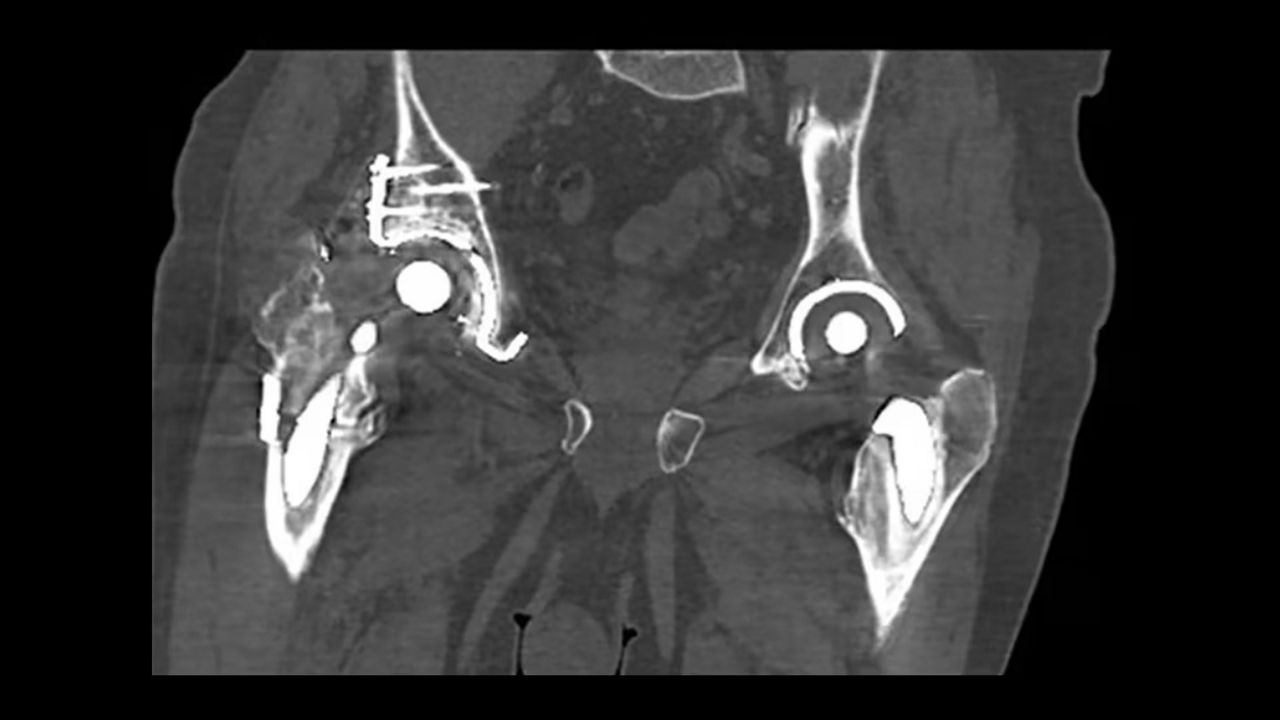

Streamline and automate your RT planning workflow.

<p>Auto Segmentation</p>

Learn more

<p>Deviceless 4D</p>

<p>Advantage 4D</p>

<p>Prospective Gating</p>